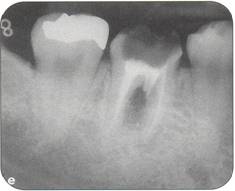

Fi 545e45f g 5-1f After extraction offirst molar from the recipient site. Fi 545e45f g 5-1 g The donor tooth. Note the adequate root form and amount of periodontal ligament on the root. Fi 545e45f g 5-1 h Measurement of the mesiodistal width of the donor tooth. |

Fi 545e45f g 5-1 i Measurement of the mesiodistal width of the recipient site. If the mesiodistal width of the donor tooth is greater than that of the recipient site, the proximal walls of the adjacent teeth are reduced to fit the donor tooth. Fi 545e45f g 5-1j Preparation of the recipient site. Removal of alveolar septum is done with a minirongeur. Fi 545e45f g 5-1 k After removal of the alveolar septum. |